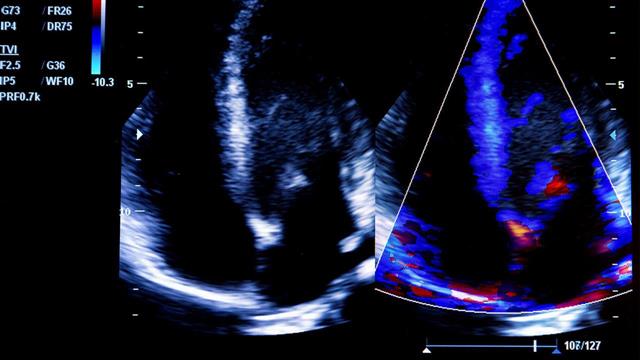

Ήδη, από την έναρξη της πανδημίας διαπιστώθηκε ότι οι ασθενείς με καρδιακές παθήσεις είχαν τον υψηλότερο κίνδυνο νοσηλείας, διασωλήνωσης αλλά και θανάτου μεταξύ των νοσούντων από COVID-19, ενώ οι ασθενείς με ιστορικό καρδιαγγειακών νοσημάτων περιλαμβάνονται στις ευπαθείς ομάδες πληθυσμού με τον υψηλότερο κίνδυνο επιπλοκών και θνητότητας. Το φάσμα των καρδιακών συνοσηροτήτων που αυξάνουν το κίνδυνο επιπλοκών από τη λοίμωξη COVID-19 εκτείνεται από την αρτηριακή υπέρταση έως την καρδιακή ανεπάρκεια.

Οι συγγραφείς μελέτησαν 912 τριπλά εμβολιασμένους ασθενείς οι οποίοι διαγνώσθηκαν με λοίμωξη COVID-19 κατά τη διάρκεια του κύματος μετάδοσης των μεταλλάξεων Όμικρον σε ένα τριτοβάθμιο πανεπιστημιακό νοσοκομείο των ΗΠΑ. Μεταξύ αυτών το 16% ανέπτυξε βαριά λοίμωξη COVID-19 και χρειάστηκε να νοσηλευτεί. Η αρτηριακή υπέρταση, η παρουσία καρδιακής ανεπάρκειας καθώς και το προηγούμενο ιστορικό εμφράγματος του μυοκαρδίου υπερδιπλασίασαν τον κίνδυνο νοσηλείας από τη λοίμωξη COVID-19.

Ωστόσο η συσχέτιση μεταξύ της αρτηριακής υπέρτασης και του κινδύνου επιπλεγμένης λοίμωξης COVID-19 παρέμεινε ισχυρή και μεταξύ ασθενών που δεν είχαν άλλες καρδιαγγειακές παθήσεις. Ο κίνδυνος ανευρέθηκε αυξημένος σε ασθενείς μεγαλύτερης ηλικίας ενώ η χορήγηση αντι-υπερτασικών φαρμάκων όπως οι αναστολείς μετατρεπτικού ενζύμου αγγειοτενσίνης και οι αναστολείς υποδοχέων αγγειοτενσίνης δεν επηρέασαν τον κίνδυνο νοσηλείας και επιπλοκών από λοίμωξη COVID-19.

Τα δεδομένα αυτά καταδεικνύουν ότι αφενός η λοίμωξη με COVID-19 δύναται να απορρυθμίσει την υποκείμενη καρδιακή νόσο, αλλά και οι συνοσηρότητες που ανευρίσκονται μεταξύ ασθενών με καρδιαγγειακά νοσήματα δημιουργούν ένα επικίνδυνο υπόβαθρο που μπορεί να οδηγήσει σε σοβαρές βραχυπρόσθεσμες αλλά και μακροπρόθεσμες επιπλοκές.